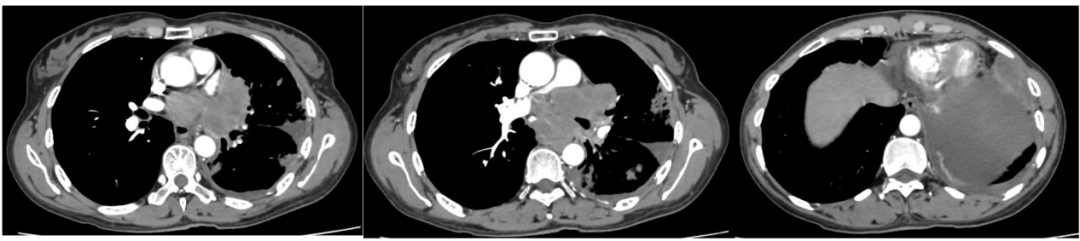

2021年1月14日行胸腹部增强CT。

图1. 2021年1月14日胸腹部CT

图像